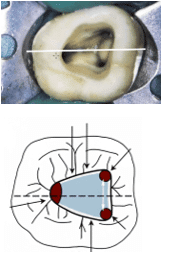

The access cavity should allow instruments to enter the root canal system in a direct, straight line, minimizing unnecessary angles or curves.

3. Symmetry of Access

The cavity should follow the natural anatomy of the pulp chamber. Symmetry provides a predictable path for instruments and helps locate orifices efficiently.